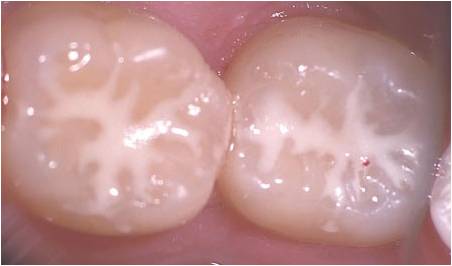

Fissure sealants are tooth coloured and applied to biting surfaces of children's teeth to prevent decay. Studies have shown that the younger the age that you bring your child to the dental practice, even if just for a check-up, the more likely they are to have a positive experience and grow up not to be afraid of the dentist.